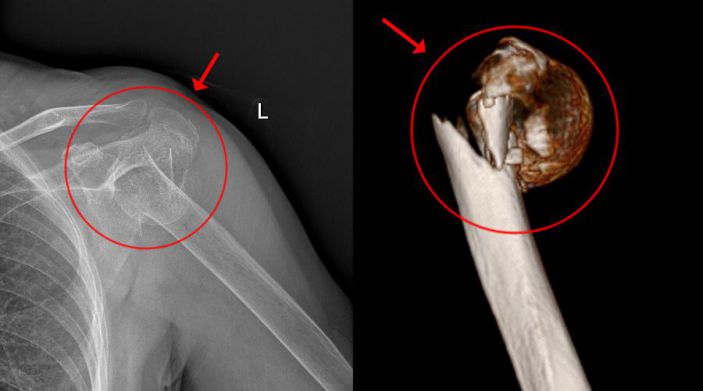

經CT檢查發現,患者的左肱骨上段粉碎性骨折,骨盆左恥骨上下肢骨折。此外,老太太還伴有老年性骨質疏松、雙側頸動脈明顯粥樣硬化、高血壓病、高脂血症等疾病。

吳主任根據CT+三維重建先行拟訂詳細的手術方案。9月4日在經過充分的術前準備後,老太太被送進了層流淨化手術室,行左側人工肱骨頭置換術。家屬在手術室外焦急地等待,而此時手術室内的吳志斌主任在麻醉科的配合下,根據方案有條不紊地開展手術,娴熟地取出左肱骨頭,并給予安裝肱骨假體,考慮到患者骨質疏松明顯,吳主任還特地加用了骨水泥。術中老太太未出現血壓下降及意識改變等其他不适,整個手術非常順利,再次給患者家屬滿意的答卷。經過醫護人員的對症治療、精心護理,老太太将于近日康複出院。

△術前